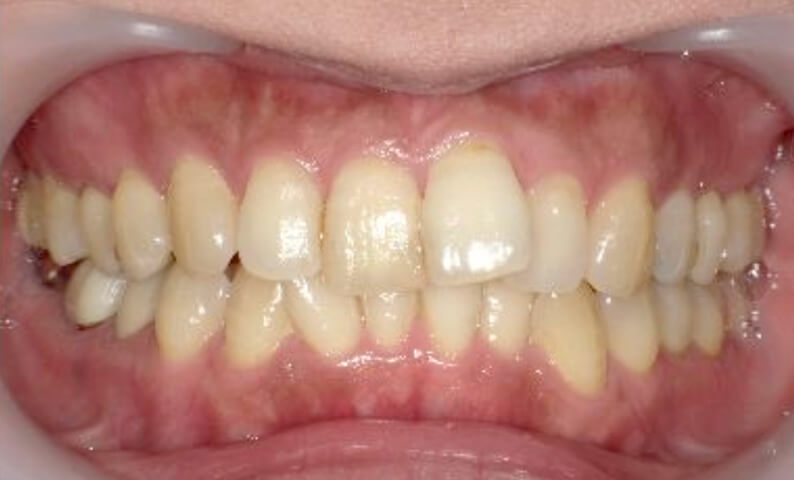

症例_002 上顎だけの部分矯正

治療期間:7ヶ月金額:30万円+税女性前歯のガタガタ上の前歯だけ

| Before | After |

|---|---|

|